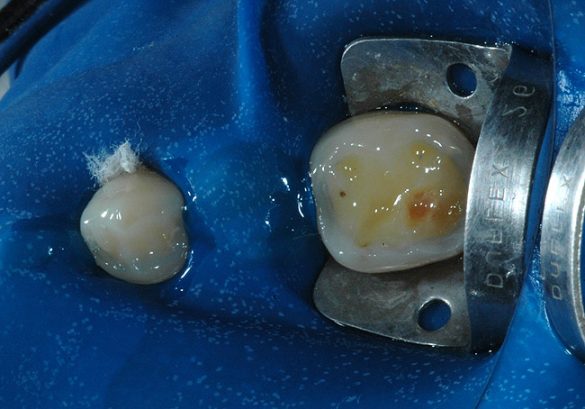

Aria posterioară a lingurii din acetat a fost secţionată în regiunea caninului şi a primului premolar şi piesele au fost utilizate pentru a restaura dinţii posteriori. S-au selectat culorile A2 pentru dentină şi A2E pentru smalţ. Cavităţile preparate pentru leziunile de coroziune au fost limitate prin îndepărtarea restaurărilor preexistente. S-a optat pentru izolarea absolută cu digă a câmpului de lucru, intercalând dinţii pentru a evita contactul compozitului cu suprafeţele aproximale. După profilaxia cu pulbere, suprafeţele de smalţ au fost gravate cu acid fosforic 37% timp de 30 secunde (fig. 5). După clătirea cu sprayul de apă/aer pentru 30 secunde, s-a aplicat un adeziv autogravant pe smalţ şi pe dentină şi s-a polimerizat cu lampa cu halogen la 500mW/cm2 timp de 20 secunde (fig. 6).

Răşina de compozit a fost inserată iniţial în regiunea restaurării de amalgam şi fotopolimerizată cu un dispozitiv halogenic timp de 20 secunde (fig. 7). Apoi s-a distribuit o porţie mai mare de compozit pe toate suprafeţele ocluzale. Şablonul a fost apoi completat cu compozitul răşinic şi s-a poziţionat la nivelul segmentului de restaurat. Fotoactivarea s-a efectuat 40 secunde (fig. 8). După polimerizare, excesul de compozit a fost înlăturat cu o freză diamantată şi discuri abrazive.